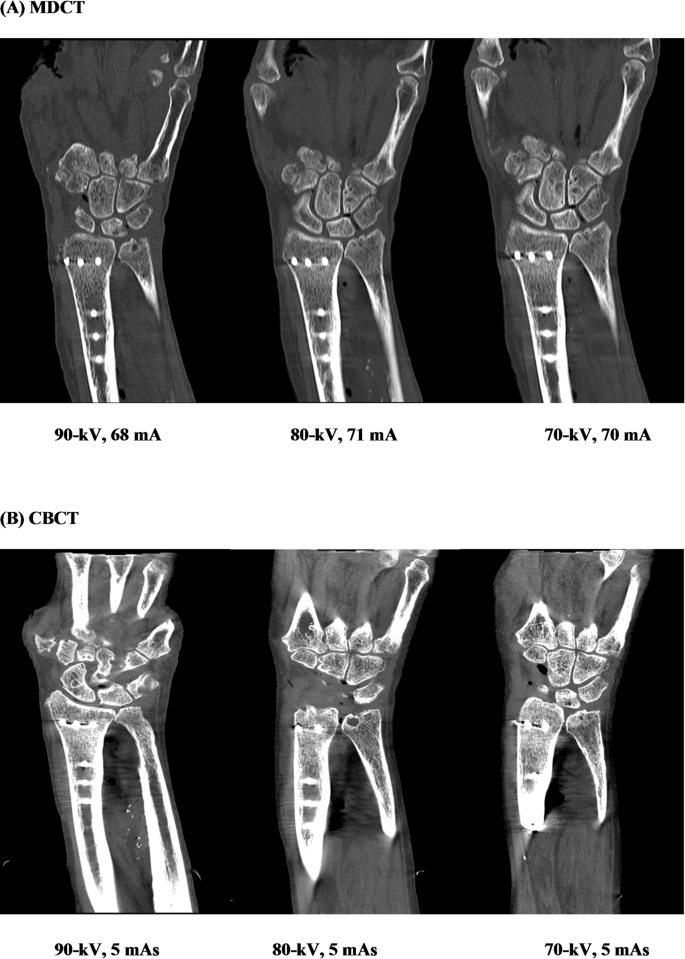

Figure 6 illustrates a visual comparison between MDCT (A) and CBCT (B) images acquired at different kV and mA/mAs settings, highlighting the impact of scan parameters on image quality and diagnostic clarity.

Representative MDCT (A) and CBCT (B) images acquired using different tube voltage and tube current settings. Images illustrate differences in image quality and metal-related artifact expression in the presence of a distal radius plate.

Subjective image quality

Subjective image quality assessments were performed by five independent radiologists using a 5-point Likert scale. CBCT performed better than MDCT on many factors, as shown in Table 3; Fig. 4.

Cortical bone visualization showed no significant difference between the modalities (mean scores: CBCT 3.9, MDCT 4.0; p = 0.28). In contrast, CBCT was rated significantly better for visualizing cancellous bone (CBCT 4.12, MDCT 3.83; p = 0.006), reducing metal-related artifacts (p = 0.0032), and achieving higher overall image quality (CBCT 4.14, MDCT 3.90; p = 0.01). The only exception was under standard protocol settings, where both modalities received equal artifact ratings.